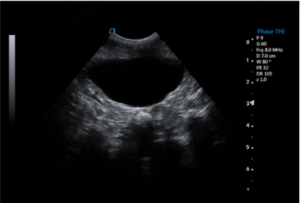

| Imaging Quality | Clear 2D, stable grayscale, optional Color Doppler for abdominal, cardiac, reproductive exams | Ensure system covers most frequent clinical exams |

Common Clinical Applications

▸ Abdominal examinations (liver, kidneys, bladder, spleen)

▸ Pregnancy diagnosis & reproductive monitoring

▸ FAST & emergency ultrasound assessments

▸ Basic cardiac screening

▸ Routine follow-up & monitoring